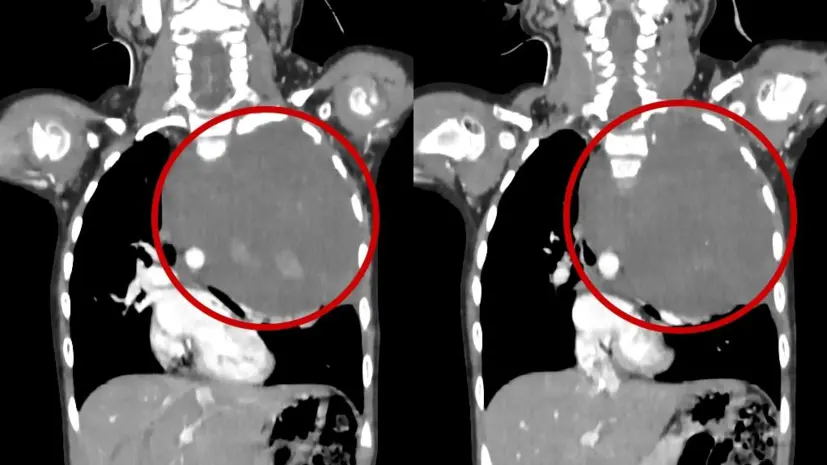

Компьютерная томография показала, что у малышки в грудной клетке притаилась огромная опухоль. Новообразование шириной 10 на 12 сантиметров распространялось в подключичную область и шею, занимая почти три четверти всей плевральной полости. Столь массивный опухолевый узел не просто заполнил внутреннее пространство — он угрожал сместить аорту, сдавливал сердце и легкое, а его ткани пронизывали жизненно важные сосуды.

При поступлении в РДКБ пациенты всегда проходят повторную диагностику. Этот случай не стал исключением — каждое обследование, каждый снимок вызывали напряжение в команде врачей. Пугающие размеры опухоли оставляли мало места для маневра: аорта оказалась смещенной к центру грудной полости, а сердце и левое легкое почти полностью зажаты гигантским новообразованием.

Особую тревогу вызывало и то, что крупные сосуды — позвоночная артерия, питающая мозг, и подключичная артерия, обеспечивающая кровоснабжение руки, — пересекали опухолевую ткань. Ошибки здесь быть просто не могло.